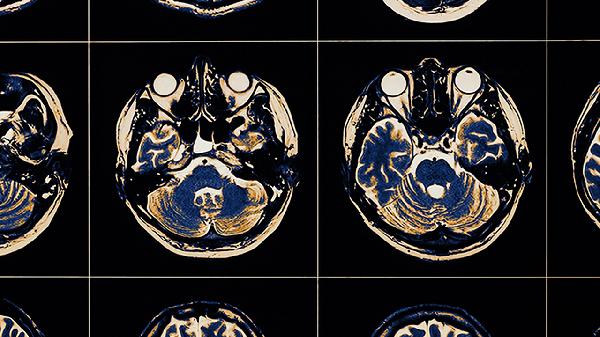

脑血栓片中的葛根素等黄酮类物质可扩张脑血管,增加脑血流量。这种作用能够缓解局部缺血缺氧状态,改善脑组织代谢。对于急性期脑血栓形成患者,可减轻神经功能缺损症状,但需配合其他治疗措施。